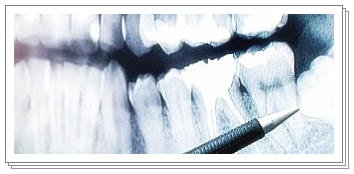

- 일부 사람들은 선천적으로 사랑니가 없는 경우도 있으며, X-ray 검사를 통해 확인할 수 있습니다.

- 이 경우, 자연스럽게 자라지 않으므로 치과에서 X-ray 촬영 후 발치 여부를 결정하는 것이 필요합니다.

- 사랑니가 자라는 과정에서 통증이 너무 심하거나, 지속적으로 불편함이 있다면 X-ray 촬영을 통해 치아 상태를 확인해야 합니다.